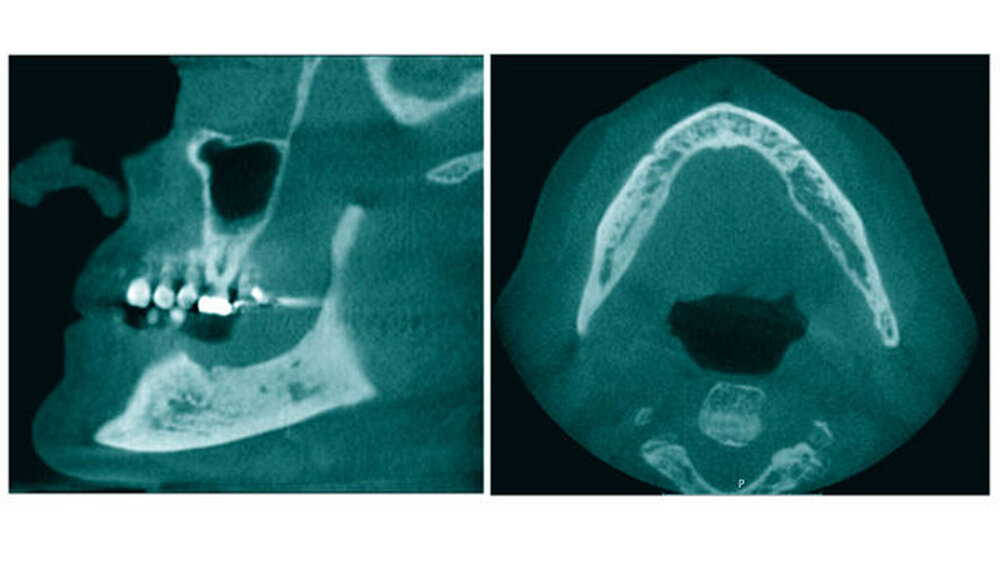

Bei einer medikamentenbedingten Osteonekrose verändert sich die räumliche Knochenstruktur des Kieferknochens. Es treten Osteosklerosen neben osteolytischen Prozessen auf, die Lamina dura ist verdickt, unter dem Periost lagert sich Knochen ab und nach Zahnextraktionen bleiben die Alveolarhöhlen röntgenologisch sichtbar und werden nicht mit Knochen aufgefüllt. Klinische Befunde unterschätzen das Ausmaß der Erkrankung häufig, mithilfe der dreidimensionalen röntgenologischen Bildgebung lässt sich die Situation besser beurteilen. Eine Aussage, ob tatsächlich eine medikamentenbedingte Osteonekrose vorliegt, ist bislang jedoch von der subjektiven Beurteilung der Bildgebung und der Klinik durch den Arzt abhängig.

Ziel einer kürzlich veröffentlichten Studie aus Mainz war es, eine objektivierbare Methode zu entwickeln, wie Patienten mit medikamentenbedingter Osteonekrose anhand von DVT-Aufnahmen identifiziert werden können. Dazu berechneten die Forscher einen speziellen mathematischen Index – die fraktale Dimension. Sie kann vereinfacht als Komplexität einer Struktur verstanden werden; je komplexer die Struktur, desto höher die fraktale Dimension.

Die Mainzer Forscher nahmen sich DVT-Aufnahmen von 77 Patienten mit bekannter medikamentenbedingter Osteonekrose (Studiengruppe) vor und verglichen definierte Regionen im Ober- und im Unterkiefer mit den gleichen Regionen auf DVT-Bildern von 78 gesunden Patienten (Kontrollgruppe). Im Unterkiefer war das die Knochenregion zwischen der Wurzelspitze der Unterkiefermolaren und dem Mandibularkanal, im Oberkiefer die Region oberhalb der Wurzelspitzen der Eckzähne. Es wurden auf den Röntgenbildern der Studiengruppe also nicht unbedingt die Regionen analysiert, bei denen schon eine medikamentenbedingte Osteoradionekrose erkennbar war.